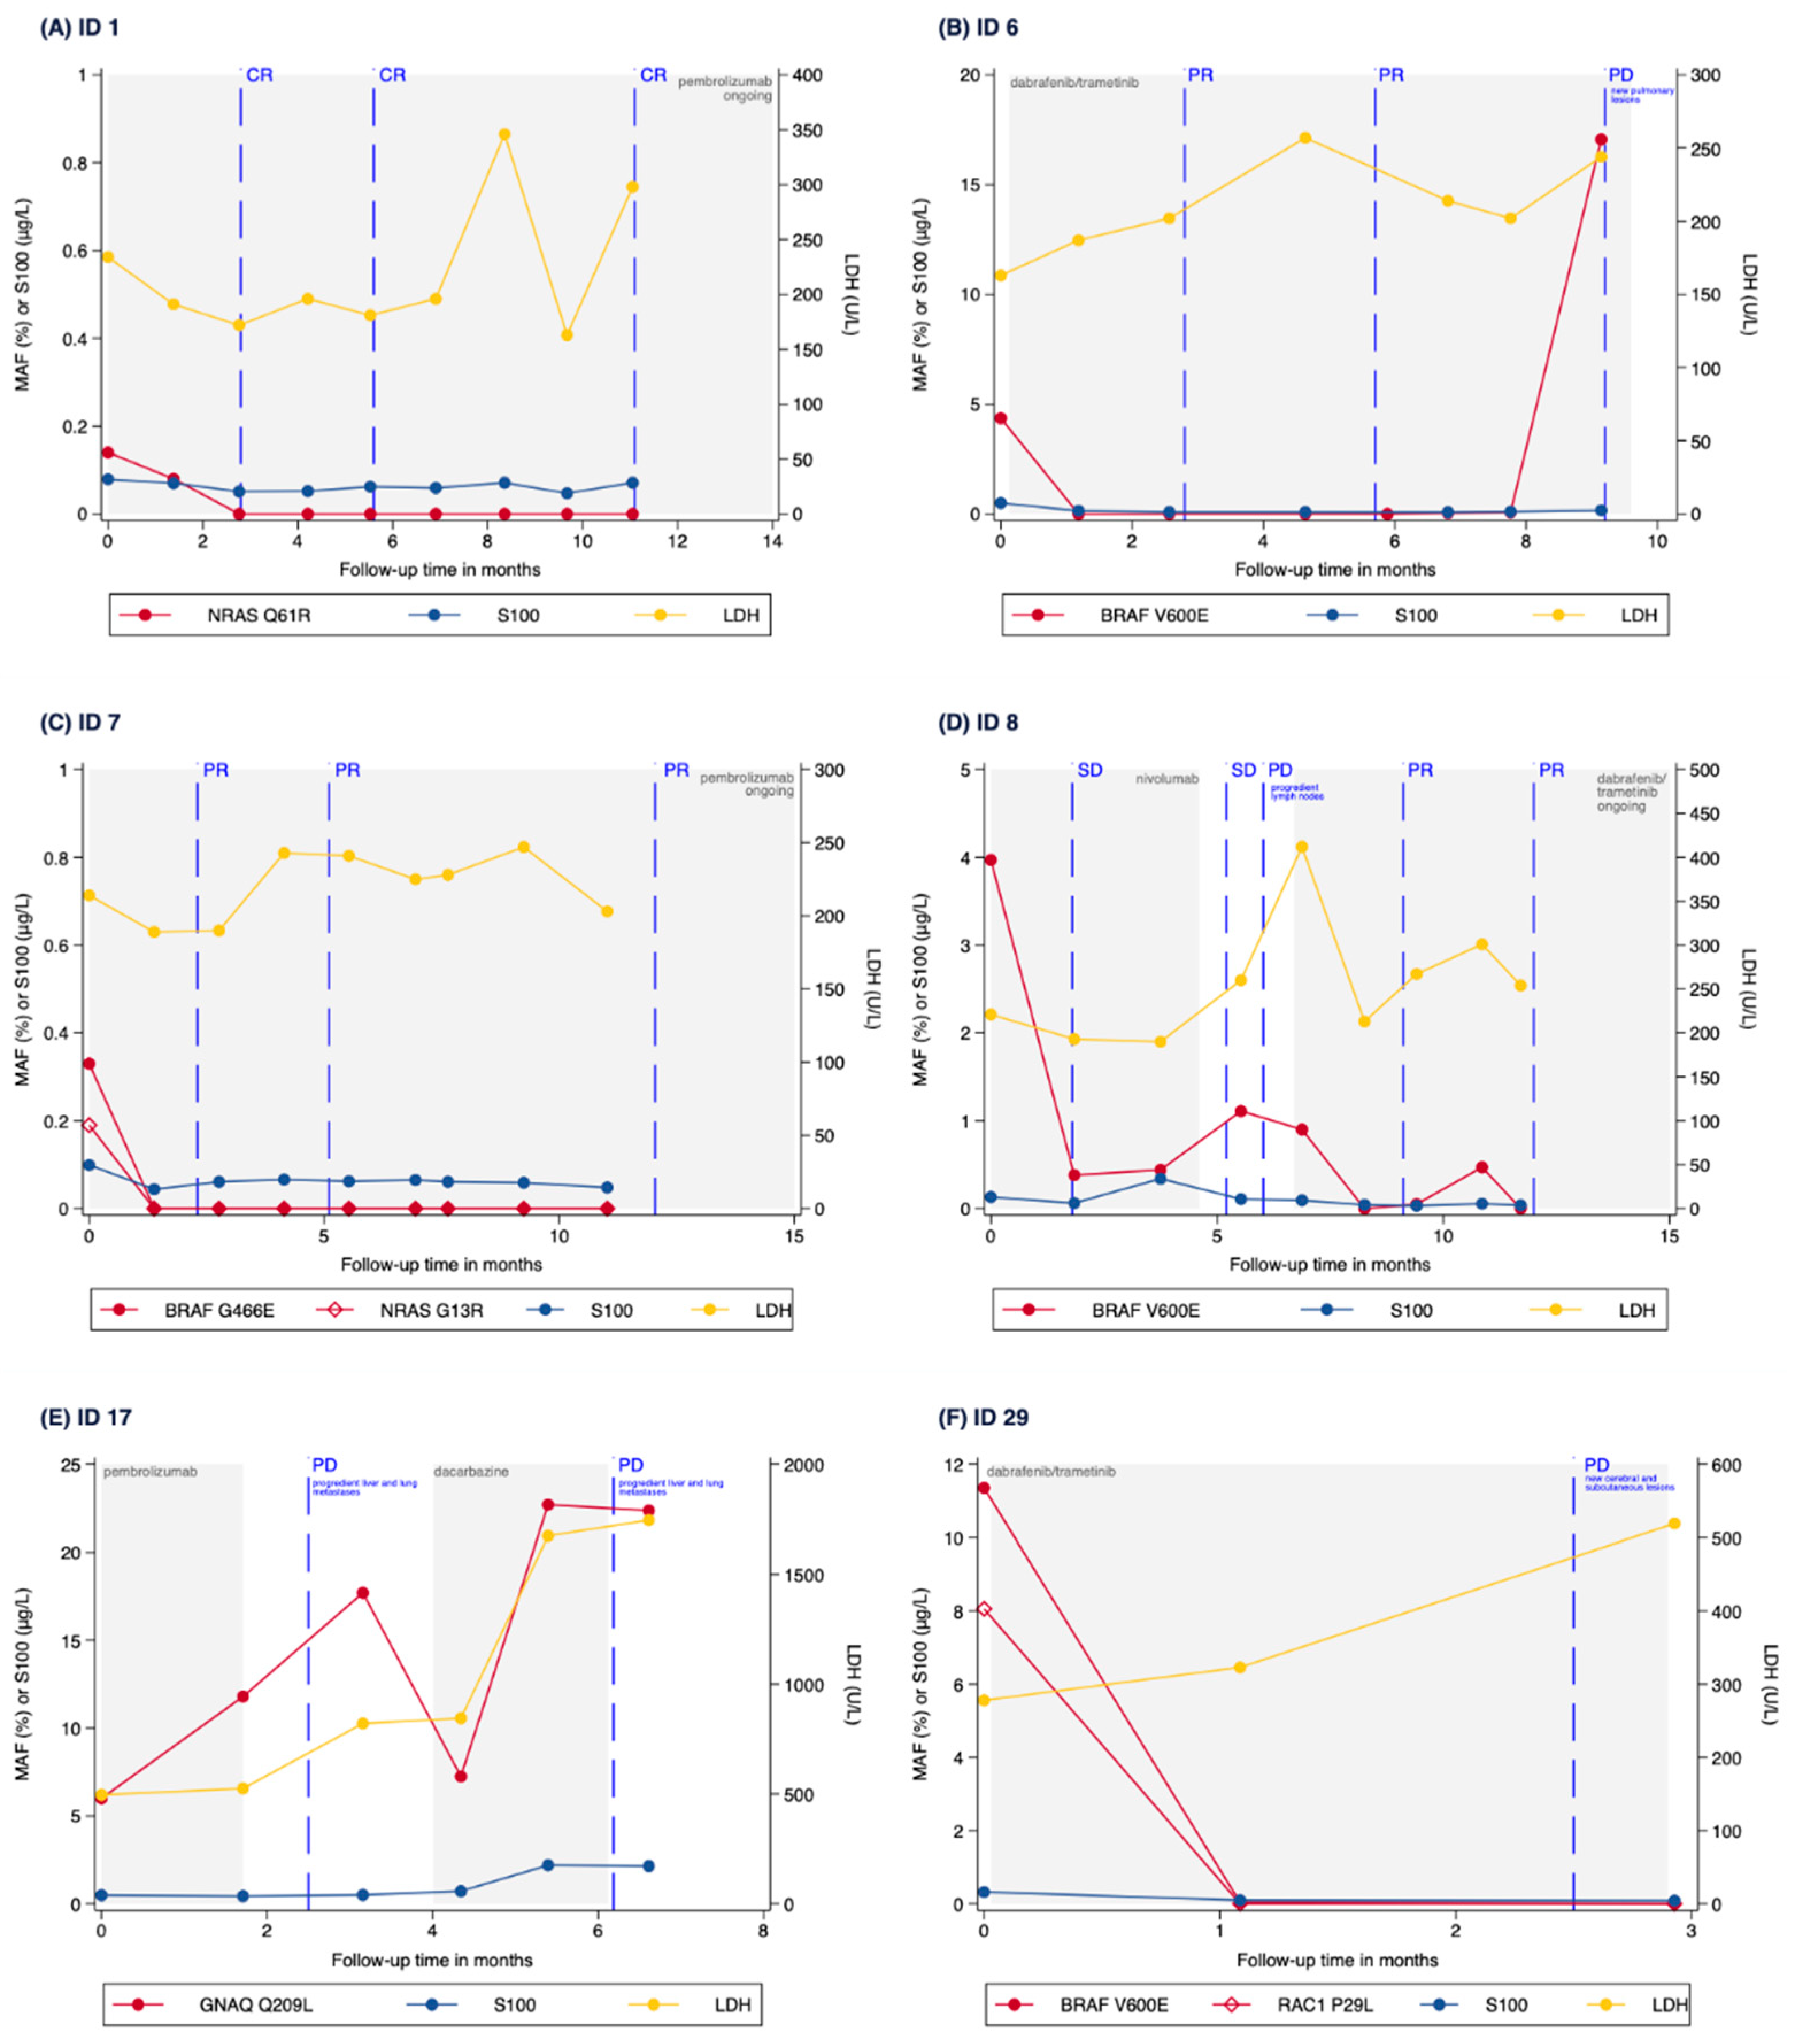

3.3. Correlation of MAF Levels with Radiological Response

3.4. Correlation of MAF Levels with S100, LDH and CRP Levels